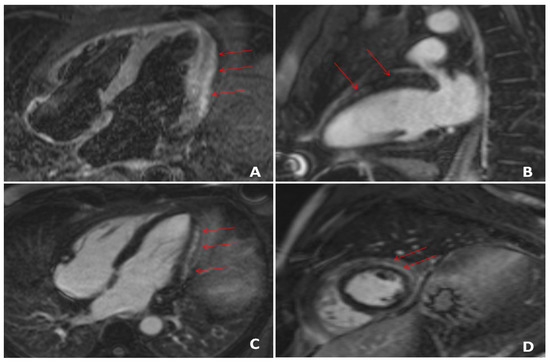

- Esposito, A.; Palmisano, A.; Natale, L.; Ligabue, G.; Peretto, G.; Lovato, L.; Vignale, D.; Fiocchi, F.; Marano, R.; Russo, V. Cardiac Magnetic Resonance Characterization of Myocarditis-Like Acute Cardiac Syndrome in COVID-19. JACC Cardiovasc. Imaging 2020, 13, 2462–2465. [Google Scholar] [CrossRef] [PubMed]

- Gravinay, P.; Issa, N.; Girard, D.; Camou, F.; Cochet, H. CMR and Serology to Diagnose COVID-19 Infection with Primary Cardiac Involvement. Eur. Heart J. Cardiovasc. Imaging 2021, 22, 133. [Google Scholar] [CrossRef]

- Luetkens, J.A.; Isaak, A.; Zimmer, S.; Nattermann, J.; Sprinkart, A.M.; Boesecke, C.; Rieke, G.J.; Zachoval, C.; Heine, A.; Velten, M.; et al. Diffuse Myocardial Inflammation in COVID-19 Associated Myocarditis Detected by Multiparametric Cardiac Magnetic Resonance Imaging. Circ. Cardiovasc. Imaging 2020, 13. [Google Scholar] [CrossRef]

- Manka, R.; Karolyi, M.; Polacin, M.; Holy, E.W.; Nemeth, J.; Steiger, P.; Schuepbach, R.A.; Zinkernagel, A.S.; Alkadhi, H.; Mehra, M.R.; et al. Myocardial Edema in COVID-19 on Cardiac MRI. J. Heart Lung Transplant. 2020, 39, 730–732. [Google Scholar] [CrossRef]

- Caballeros Lam, M.; de la Fuente Villena, A.; Hernández Hernández, A.; García de Yébenes, M.; Bastarrika Alemañ, G. Cardiac Magnetic Resonance Characterization of COVID-19 Myocarditis. Rev. Esp. Cardiol. Engl. Ed. 2020, 73, 863–864. [Google Scholar] [CrossRef] [PubMed]